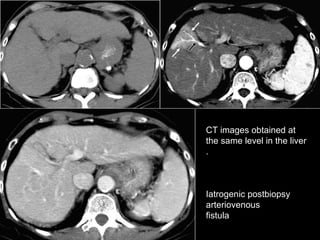

CT images obtained at the same level in the liver.  Iatrogenic postbiopsy arteriovenous fistula

CT images obtainedat the same level in the liver. Iatrogenic postbiopsy arteriovenous fistula